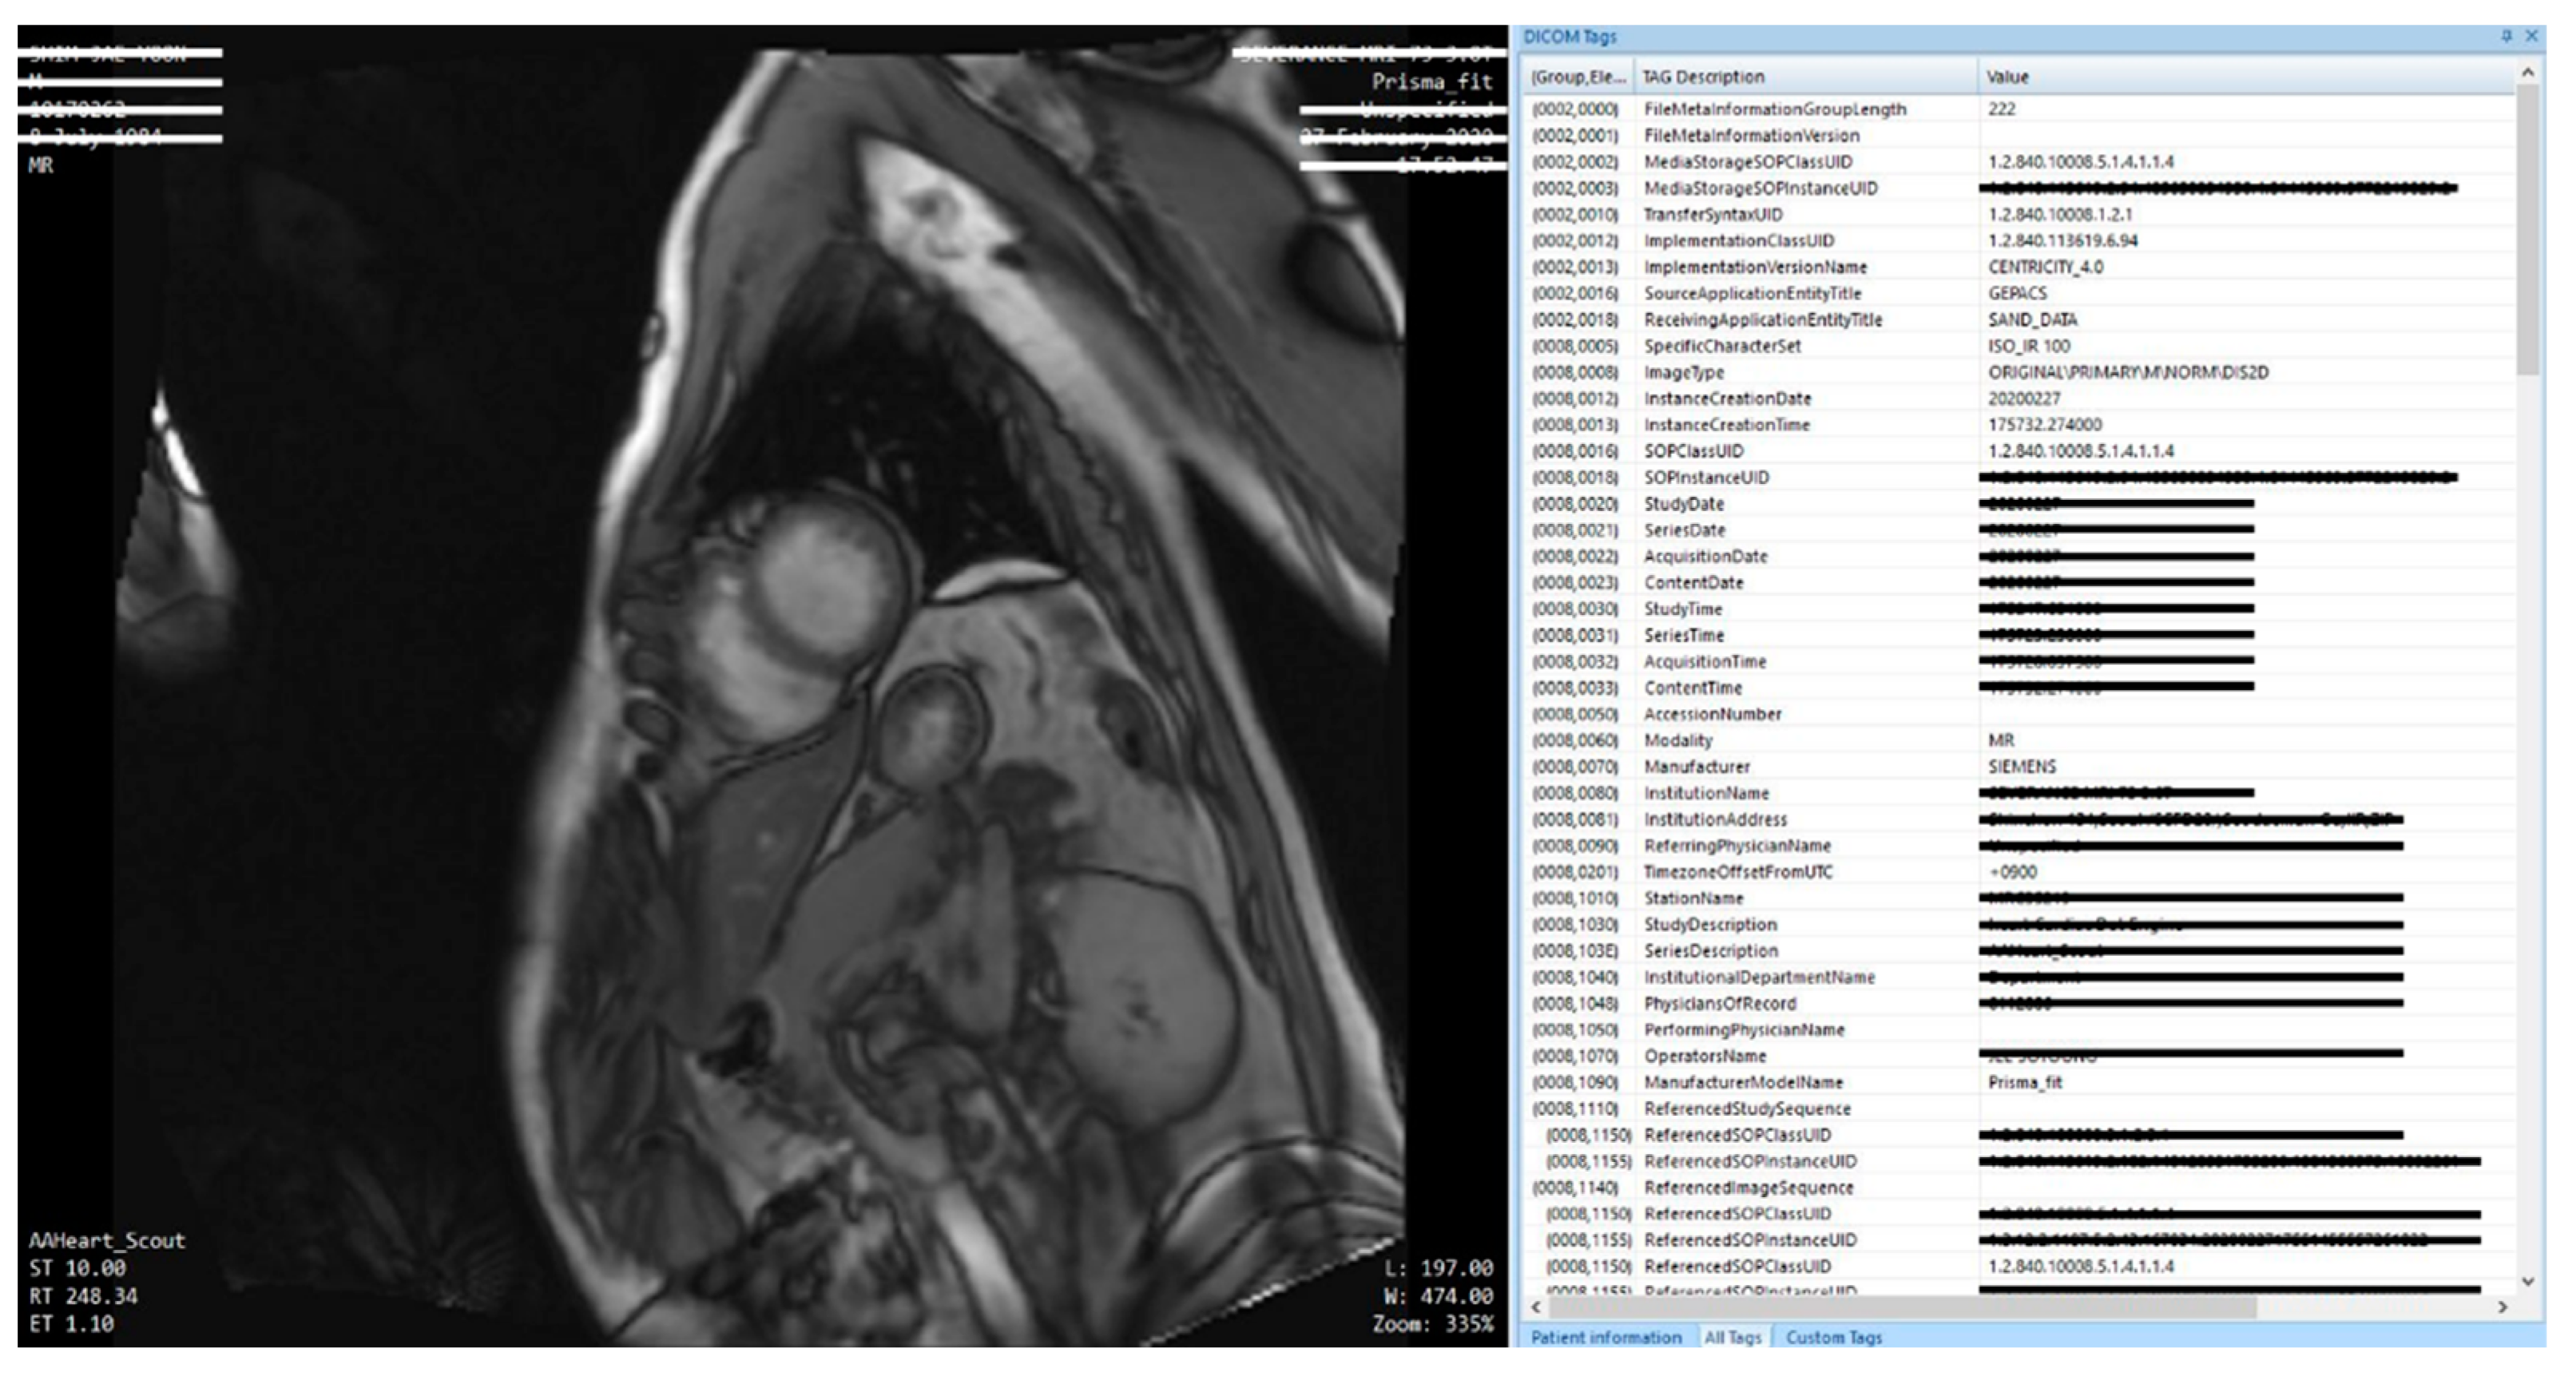

When comparing MRI data using the CTP from the original to the data after the de-identifier process, data that are at risk of personal information leaks are either removed or de-identified.

In Figure 10, data that needs to be protected for personal information related issues is redacted in the cardiovascular MRI original image. Redacted information are items related to DICOM de-identifier methods and basic profile and include the patient’s name, MR imaging location, name of the specialist, and date of imaging, among others. Information processes by de-identifier processes are shown in Figure 11.

In Figure 11, data elements that were shown in the original are nonexistent or changed to different value. The risk of personal information leaks are minimized and only information needed for research is retained.